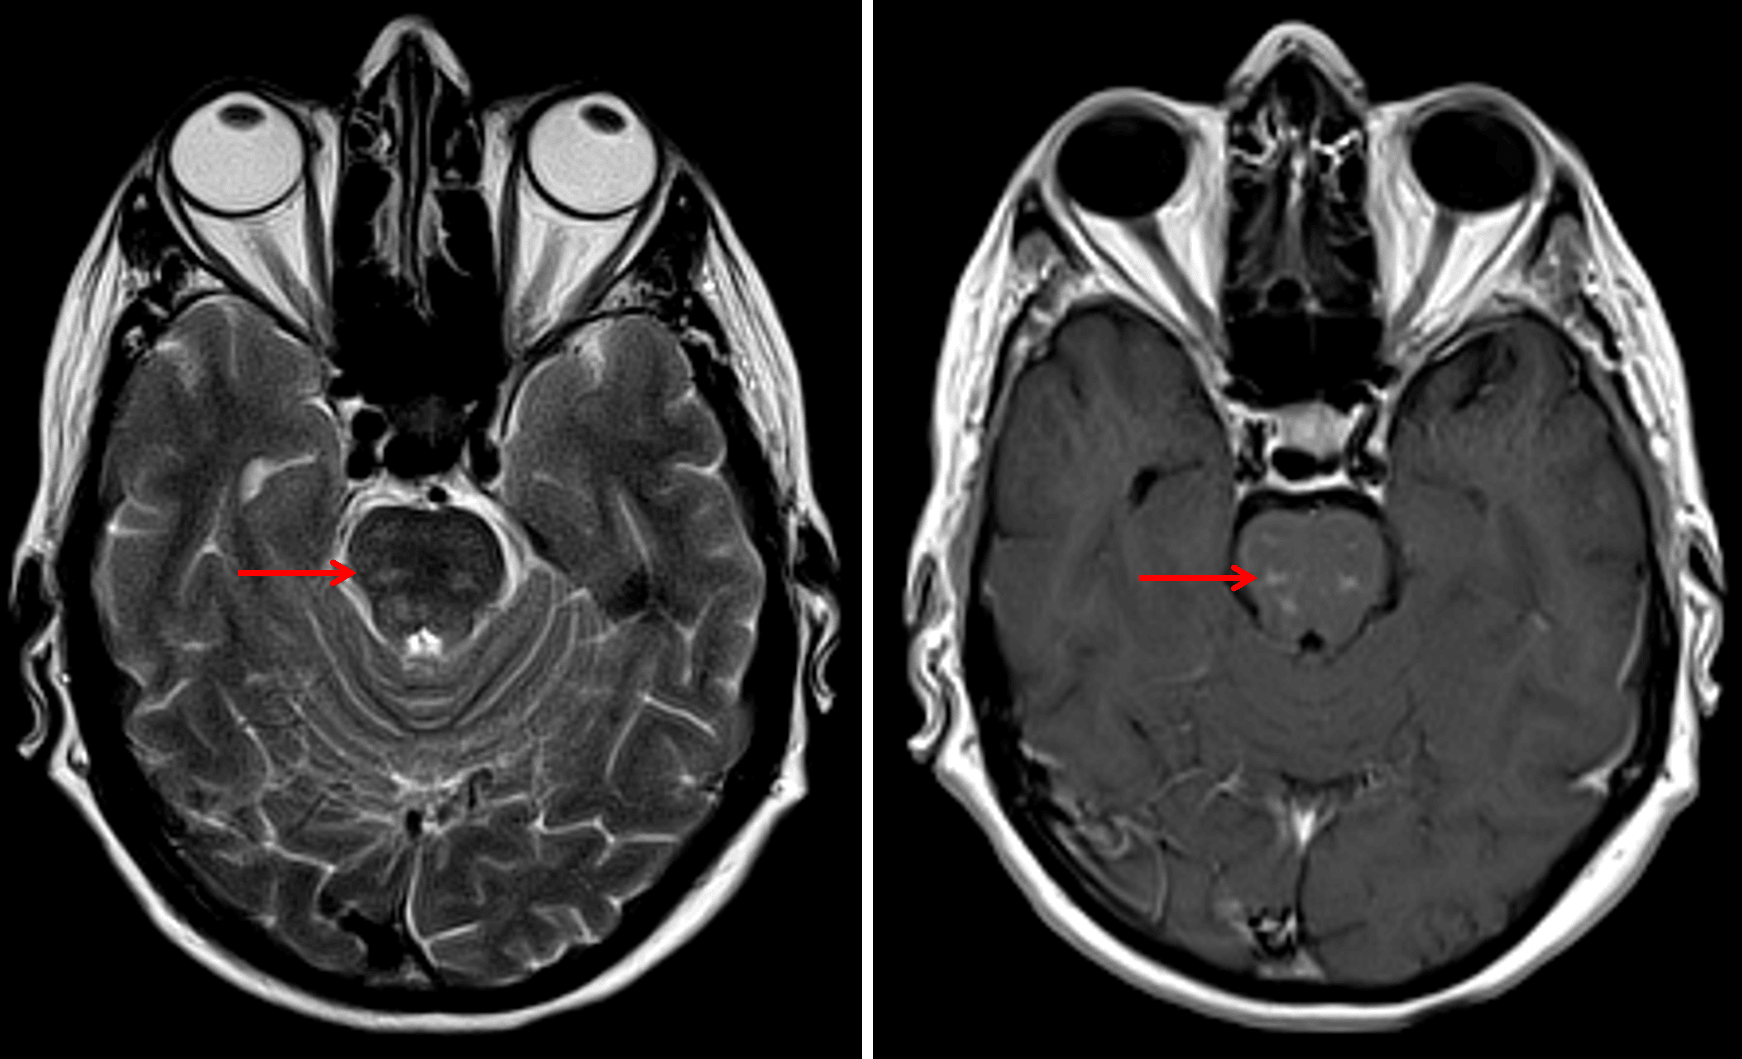

Relatively symmetric patchy T2 signal hyperintensity and enhancement in the pons (red arrows), which is a typical imaging appearance for CLIPPERS.